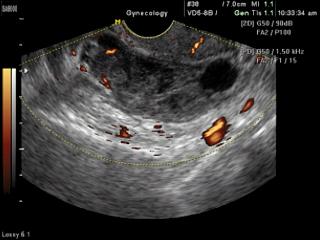

Ectopic pregnancy, power doppler

SonoAce-8000. Ectopic pregnancy, power doppler.